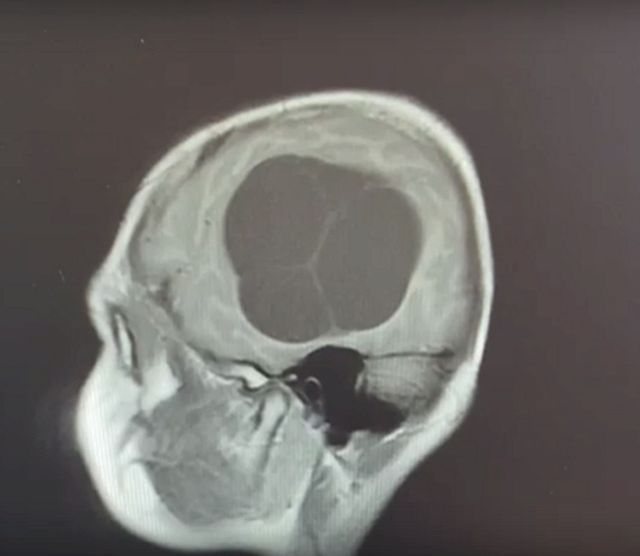

В частной клинике мальчику сделали МРТ головного мозга. На снимках врачи увидели объемное образование, которое заняло большую часть правого полушария. Однако диагноз ребенку поставить смогли только специалисты ЧОДКБ.

«Когда мальчик пришел ко мне, я очень удивился, взглянув на снимки МРТ. Эхинококкоз головного мозга. Количество кист не поддавалось подсчету», - рассказал заведующий отделением нейрохирургии ЧОДКБ Герман Сафронов.